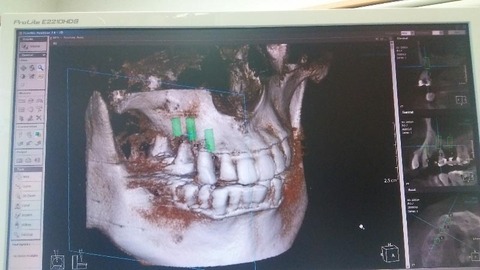

そして、ジャジャジャーン、CTスキャンで私の顎を中心に、頭骸骨のレントゲンを撮る↓。

先生は、これを観て、歯石をとった後の最終処置として、根が浮いている3番とすでに抜けた4番の隣の5番を抜いて、3本の人工歯根を立て、その歯根に4本の歯を装着するといという計画を提案しました。人工歯根の位置は、下の写真の緑色の位置です。

この計画を了承しました。5番は残したかったけど、根が浅く浮き気味なので、泣き泣き諦めることにしました(T_T)。